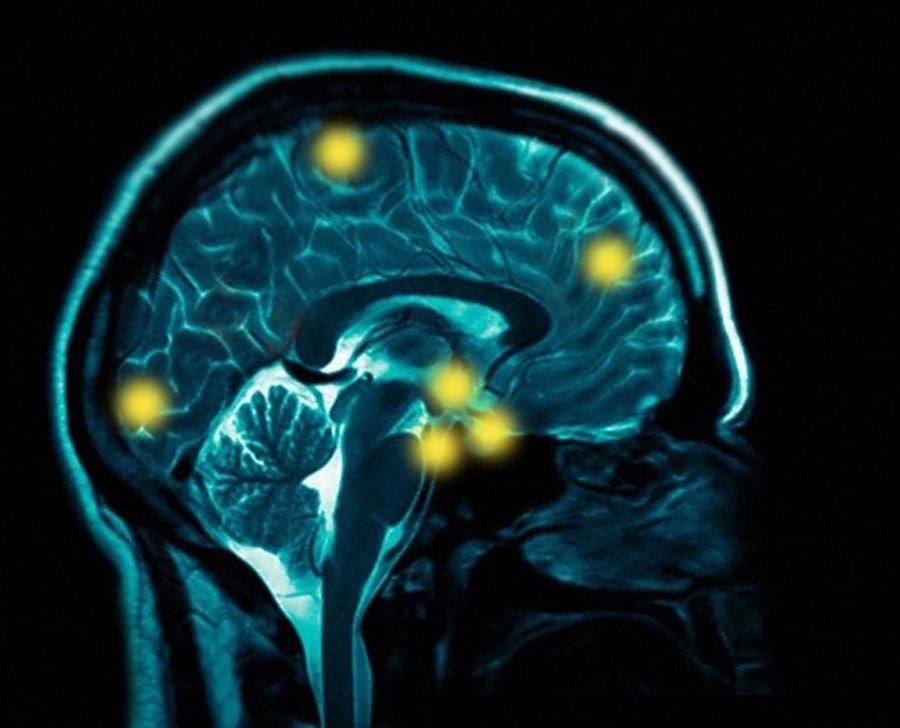

Az agy „kikérdezése” vizsgálattal

Elektródák használatával sikerült behatolni egész az egyes idegsejtekig és oszcillográfon regisztrálni reakcióikat. Az agyat alkotó neuronok hatalmas tömegét vetették alá hasonló „kikérdezésnek”. Ily módon tisztázták, hogy már az egyes idegsejtek különböző bonyolult funkciókat teljesíthetnek, mint például az ingerkeltők megkülönböztetése, megjegyzése, a rájuk való reagálás stb. De ha az inger monoton ismétlődik, a neuron fokozatosan megszűnik válaszolni rá: elektromos válaszreakciói kialszanak. Az ilyen agyi idegsejteket újdonság-neuronoknak nevezik. Az elektrofiziológiai módszer lehetővé tette, hogy ne csak tevékenységük végső megnyilvánulásai alapján (a tettekből és a szavakból) ítéljük meg az agyi struktúrák funkcionális állapotát, hanem közvetlenül is felmérjük ezt az állapotot.Egy meghatározott pszichikus funkció anyagi szubsztrátumát nem egyetlen idegsejtnek, mezőnek, vagy akár agyi területnek, hanem sokaknak a munkája alkotja. Ennek megfelelően maga a pszichikum sem más, mint számos agyi terület aktív funkcionálásának eredménye, s ezek a területek bonyolult funkcionális és morfológiai kölcsönhatásban állnak egymással. Még a legegyszerűbb érzet keletkezése is feltételezi különböző kérgi területek és kéregalatti képződmények munkáját.Az agy egységes egészként, bonyolult funkcionális rendszer gyanánt működik. Ennek során – és ez is természetes – a kéreg és az egész agy nem lehet izolálva a periferikus idegrendszertől, a szervezettől mint egésztől. Az agyműködés helyes megértéséhez csak úgy juthatunk el, hogy szintetikusan összevetjük az egyes neuronok tanulmányozása során nyert eredményeket az ember külső viselkedésének vizsgálatából származó tapasztalatokkal.